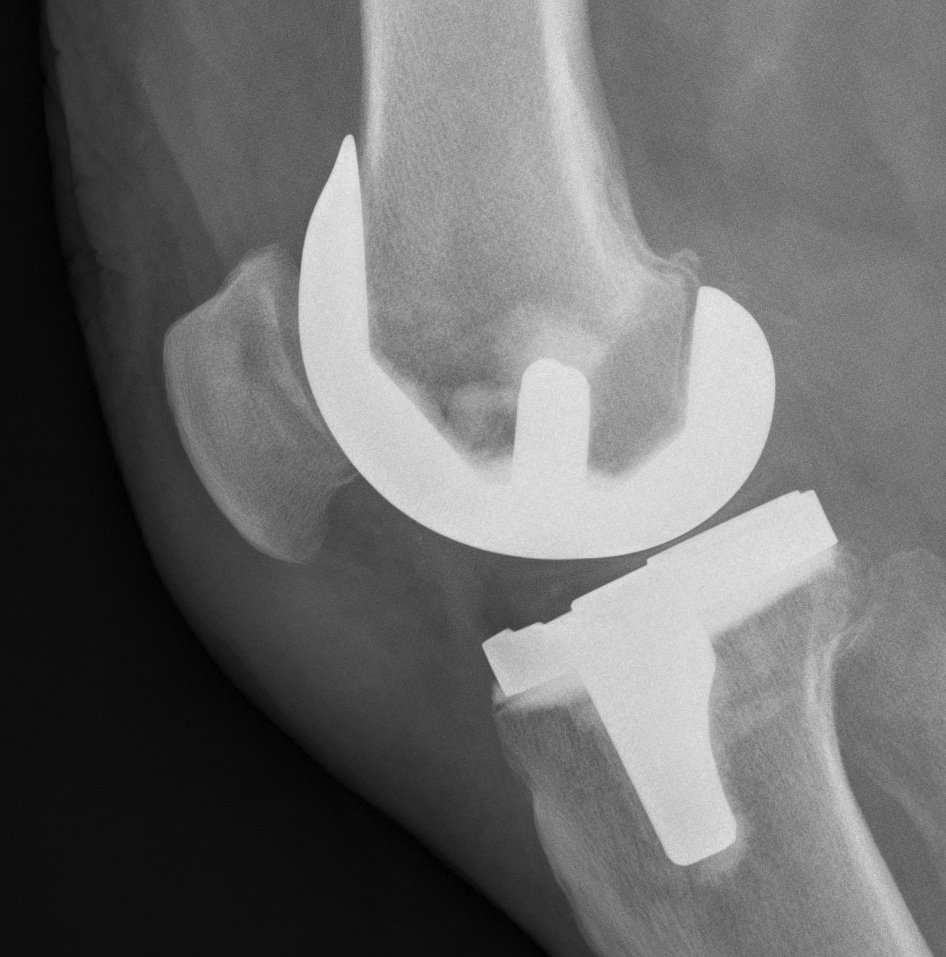

Surgical Technique

1. Appropriate component position

- femur 3o ER, lateral placement

- tibia slight ER, lateral placement

- restore mechanical axis

2. Restore thickness of patella

Under-resection

- overstuffs PFJ / anterior knee pain

- increases joint reaction force

- decreased flexion

Over-resection

- predispose to fracture

- ensure 15mm minimum

3. Avoid tilting patella

Symmetric bone resection

4. Ensure tracking well

Combination prosthetic positioning and soft tissue balancing

A. Patella button placement

- medialise component

B. Lateral Release

- assess tracking before retinacular closure

- perform lateral release if patella shows tilt or subluxation

- from "Inside Out"

- preserve LSGA if possible